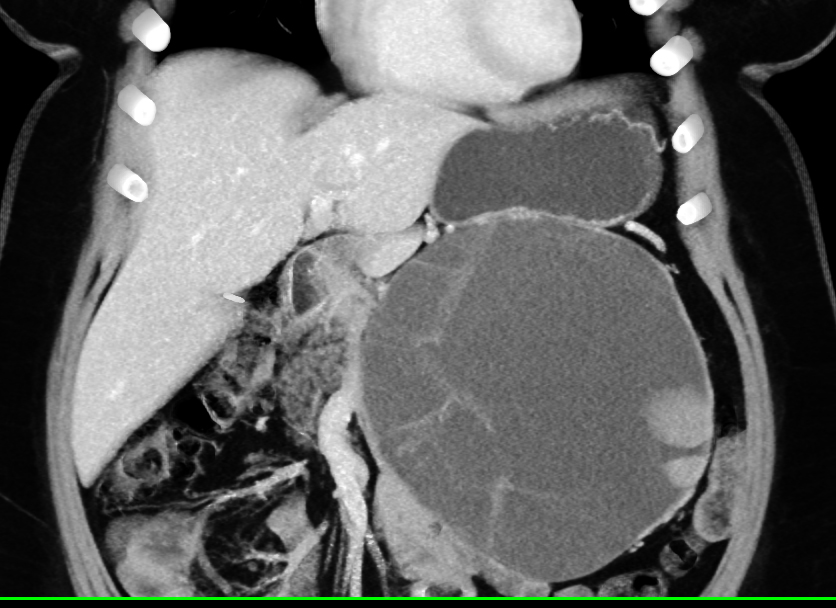

9) In this patient with small bowel GI bleed the best dx is?

angiodysplasia

GIST tumor

small bowel adenocarcinoma

metastatic melanoma